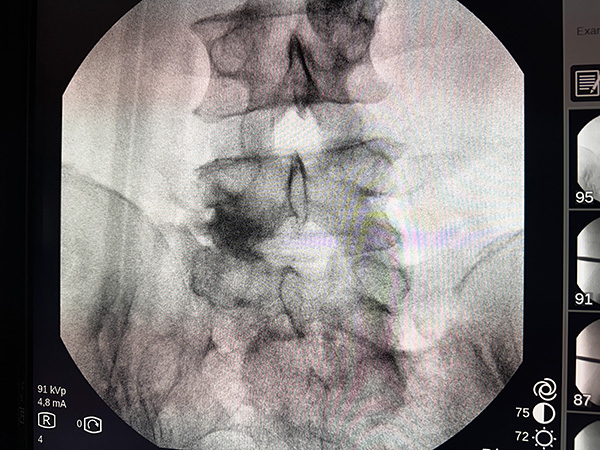

Szpital MSWiA w Kielcach ma na swoim koncie liczne sukcesy, a dr Arkadiusz Granek po raz kolejny przyczynia się do jednego z nich, wykonując – z pełnym sukcesem – jedną z pierwszych w Europie operacji w pełni endoskopowej stabilizacji kręgosłupa odcinka lędźwiowego.

Dzięki tej metodzie chory po wcześniejszej dekompresji L5/S1 z bólem korzeniowym po lewej stronie, obecnie podaje ustąpienie objawów.